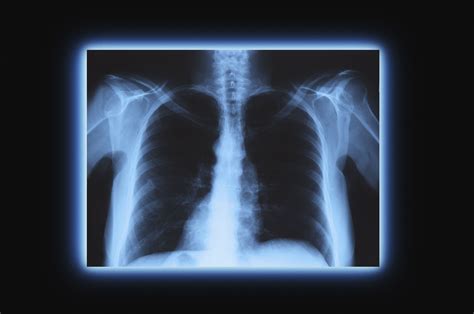

Sex X Ray technology involves the use of X-rays to produce images of the internal structures of the reproductive and sexual organs. This type of imaging is particularly useful for diagnosing conditions that affect the reproductive system, such as tumors, infections, and anatomical abnormalities. The technology works by passing X-rays through the body, which are then captured on a detector to create detailed images.

- Detecting Tumors and Cancers: X-rays can reveal the presence of tumors or cancers in the reproductive organs, allowing for early detection and treatment.

- Assessing Infections: Infections in the reproductive system, such as pelvic inflammatory disease (PID), can be identified through detailed imaging.